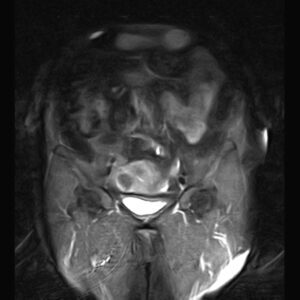

PELVIC MRI

( with & without contrast)

REPORT:

– Multiple intra mural – subserosal myoma :

1. ( 40 x 45 mm ) in right side of fondus

2. ( 20 x 22 mm ) & ( 20 x 25 mm ) in right side of body

3. ( 48 x 55 mm ) in left side of body

– Both ovaries are atrophied & without follicles .